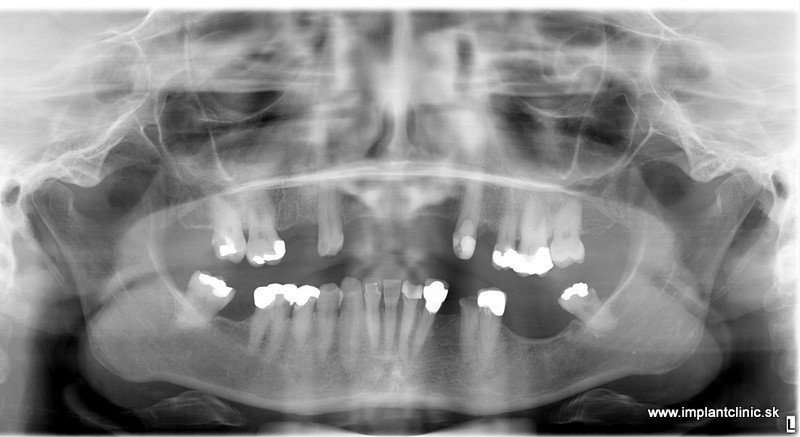

Rekonštrukciu chrupu v celkovej narkóze podstúpila aj naša pacientka Jana. Objednala sa na bezplatnú konzultáciu v Implantclinic. MUDr. Salka navrhol pacientke následovný plán ošetrenia.

Vrchná čeľusť : 5 extrakcií, 6 zubných implantátov, 12 – členný keramický mostík

Spodná čeľusť: 11 extrakcií 6 zubných implantátov 12 – členný keramický mostík